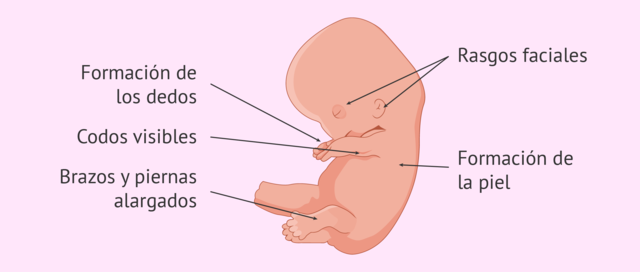

• SEMANA 8

SEMANA 8

Los rasgos faciales del embrión ya son más evidentes: se forman la nariz y el labio superior, las orejas empiezan a tomar su forma y los ojos se cubren con la piel que formará los párpados,se forma la piel, el corazón posee ya cuatro cámaras, se diferencian las válvulas aórtica y pulmonar,

Aparecen las manos con todos sus dedos, las piernas se alargan, aparecen los pies con todos sus dedos, primero las muñecas y después los tobillos,la cabeza ya no está tan desproporcionada y el cuerpo empieza a alargarse, la cara va tomando una forma más normal: los ojos migran a la parte frontal, se forman los párpados y la boca ya puede incluso abrirse,los huesos siguen su crecimiento, la cola embrionaria del final de la columna vertebral desaparece,se forma el tubérculo genital